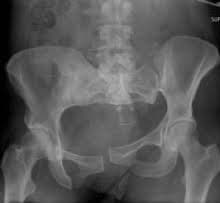

Contributor: Peter Bakes, MD

Educational Pearls: